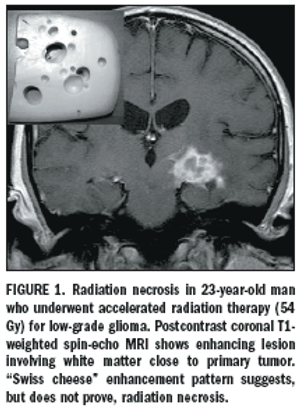

Published: December 14th 2009 | Updated: